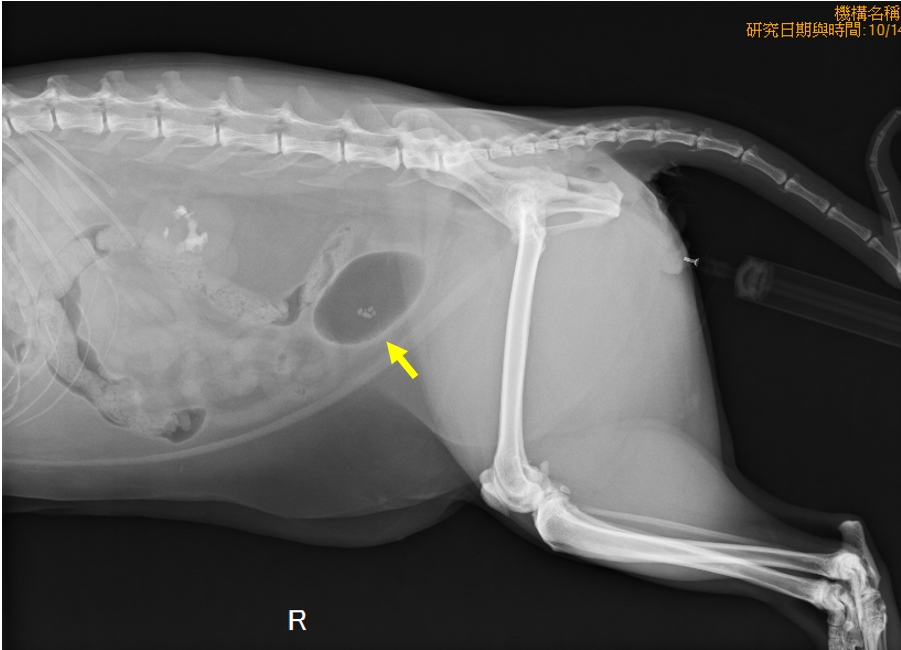

由於貓咪的體型較小,手術前會先藉由導尿將尿道中的結石沖回膀胱(圖二),再用腹腔鏡將結石取出。照片中可見腹部和膀胱切創的大小都僅約2公分寬(圖三);

圖二、導尿後,搭配負造影可見四顆結石被回推至膀胱內。